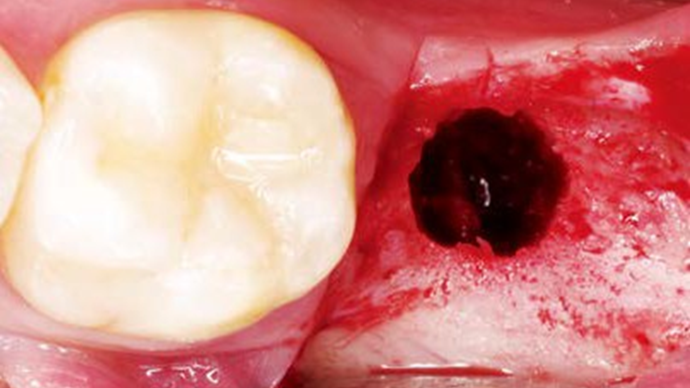

“AnyRidge implant enables fast and stable

osseointegration at this extreme case of bone defect. ”

Clinical case: Bone filling into the bottom of deepest thread at 8.0mm AnyRidge fixture

- Courtesy of Dr. Kwang Bum Park -

Keywords

AnyRidge, Knifethread ,extraction socket, ,initial stability ,Allograft, ,osseointegratio ,Dr. Kwang Bum Park, , Mandibular, Single replacement, AnyRidge, Mega-oss,

Products used

Implant system-AnyRidge, Regeneration-Mega-Oss